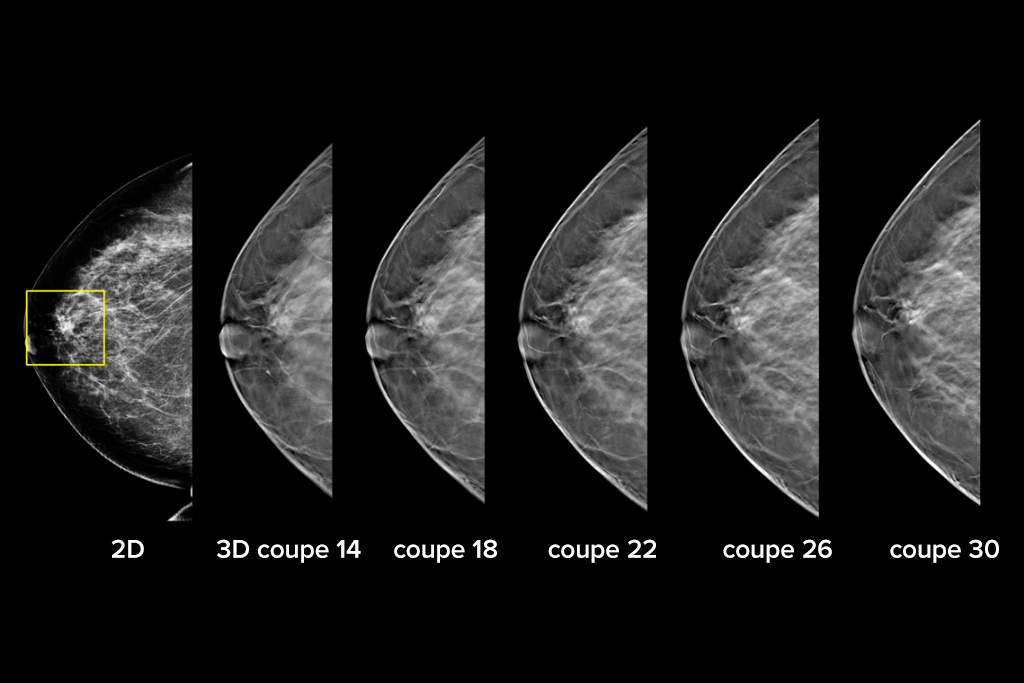

Images cliniques

Images cliniques d’une mammographie

Images cliniques d’une mammographie avec lésion suspecte

Images cliniques d’une mammographie sur un sein graisseux